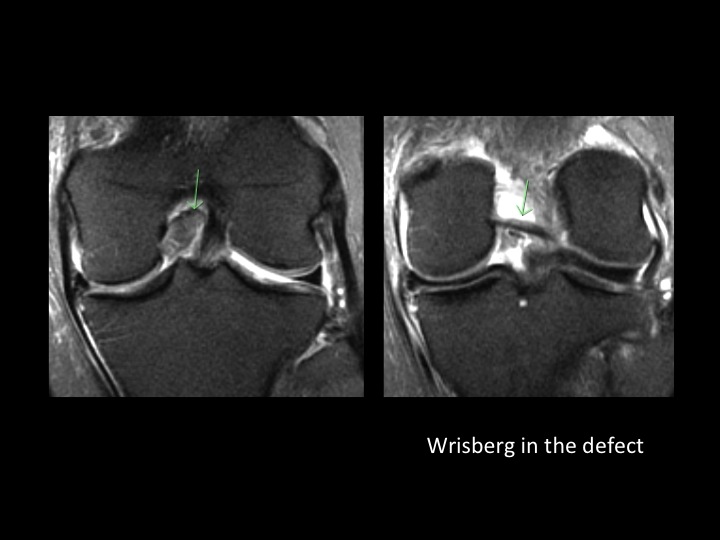

70F continued pain 4 months after fall

PCL tears rarely have a focal fluid signal defect, but typically appear thickened and frayed with increased intrasubstance signal. Despite the presence of a fluid defect in this case, I almost missed it. Ive noticed that the meniscofemoral ligaments fall into the defect, and that is what made me realize the PCL is torn. Anyone have cases they want to share? I think its a good sign. Oh, and theres a peripherally displaced meniscal flap tear with subtle remodeling of the tibial cortex. Reference article.

posterior cruciate ligament ( RID2784 )